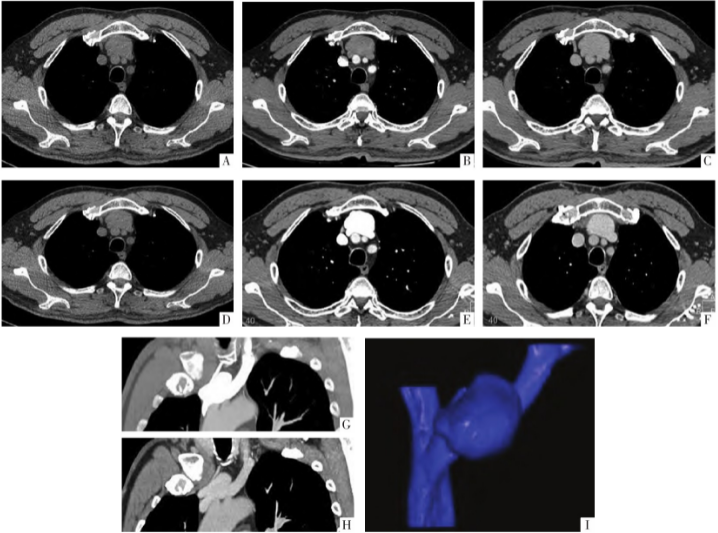

CT平扫示2例的病灶均位于上纵隔,呈类圆形,边缘光滑,其后缘紧贴邻近无名静脉。病例1首次CT增强检查时经右侧肘前静脉注射对比剂,分别于30、120 s进行增强扫描,肿块于动脉期无明显强化,延迟期呈均匀强化(图1A-C)。

图1 病人男,61岁。A图为首次CT平扫,可见上纵隔肿块,密度均匀,CT值为40 HU,边缘光滑,大小为2.4 cm×3.7 cm×2.8 cm,紧贴左侧无名静脉。B、C图为首次CT增强扫描(经右肘前静脉注射对比剂)的动脉期和延迟期,可见肿块于动脉期无明显强化,延迟期呈均匀强化,CT值分别为69、104 HU(同期相左无名静脉CT值分别为65、102 HU)。D图为第2次CT平扫影像,表现与首次(A图)一致。E、F图为第2次CT增强扫描(经左肘前静脉注射对比剂)的动脉期及延迟期,可见肿块于动脉期明显强化,延迟期强化程度减低,CT值分别为543、142 HU(同期相左侧无名静脉CT值分别为556、131 HU)。G、H图为CT增强冠状面重建影像,可见肿块与左侧无名静脉相交通。I图为伪彩图,可见肿块位于上腔静脉左侧,紧邻无名静脉。

为进一步评估肿块与左侧无名静脉的关系,3 d后再次行CT增强扫描,此次对比剂经左侧肘前静脉注入,分别于20、120 s进行扫描。病人动脉期即可见病灶内对比剂充填,局部与邻近左侧无名静脉相交通;延迟期可见病变强化程度减低,其内密度均匀,密度与左侧无名静脉血管一致,瘤腔内无充盈缺损(图1D-I)。病例2仅行1次CT增强检查,对比剂经左侧肘前静脉注射,同病例1的第2次增强CT表现一致(图2)。